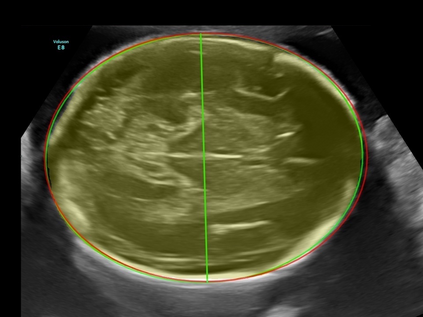

In this paper, we propose an end-to-end multi-task neural network called FetalNet with an attention mechanism and stacked module for spatio-temporal fetal ultrasound scan video analysis. Fetal biometric measurement is a standard examination during pregnancy used for the fetus growth monitoring and estimation of gestational age and fetal weight. The main goal in fetal ultrasound scan video analysis is to find proper standard planes to measure the fetal head, abdomen and femur. Due to natural high speckle noise and shadows in ultrasound data, medical expertise and sonographic experience are required to find the appropriate acquisition plane and perform accurate measurements of the fetus. In addition, existing computer-aided methods for fetal US biometric measurement address only one single image frame without considering temporal features. To address these shortcomings, we propose an end-to-end multi-task neural network for spatio-temporal ultrasound scan video analysis to simultaneously localize, classify and measure the fetal body parts. We propose a new encoder-decoder segmentation architecture that incorporates a classification branch. Additionally, we employ an attention mechanism with a stacked module to learn salient maps to suppress irrelevant US regions and efficient scan plane localization. We trained on the fetal ultrasound video comes from routine examinations of 700 different patients. Our method called FetalNet outperforms existing state-of-the-art methods in both classification and segmentation in fetal ultrasound video recordings.